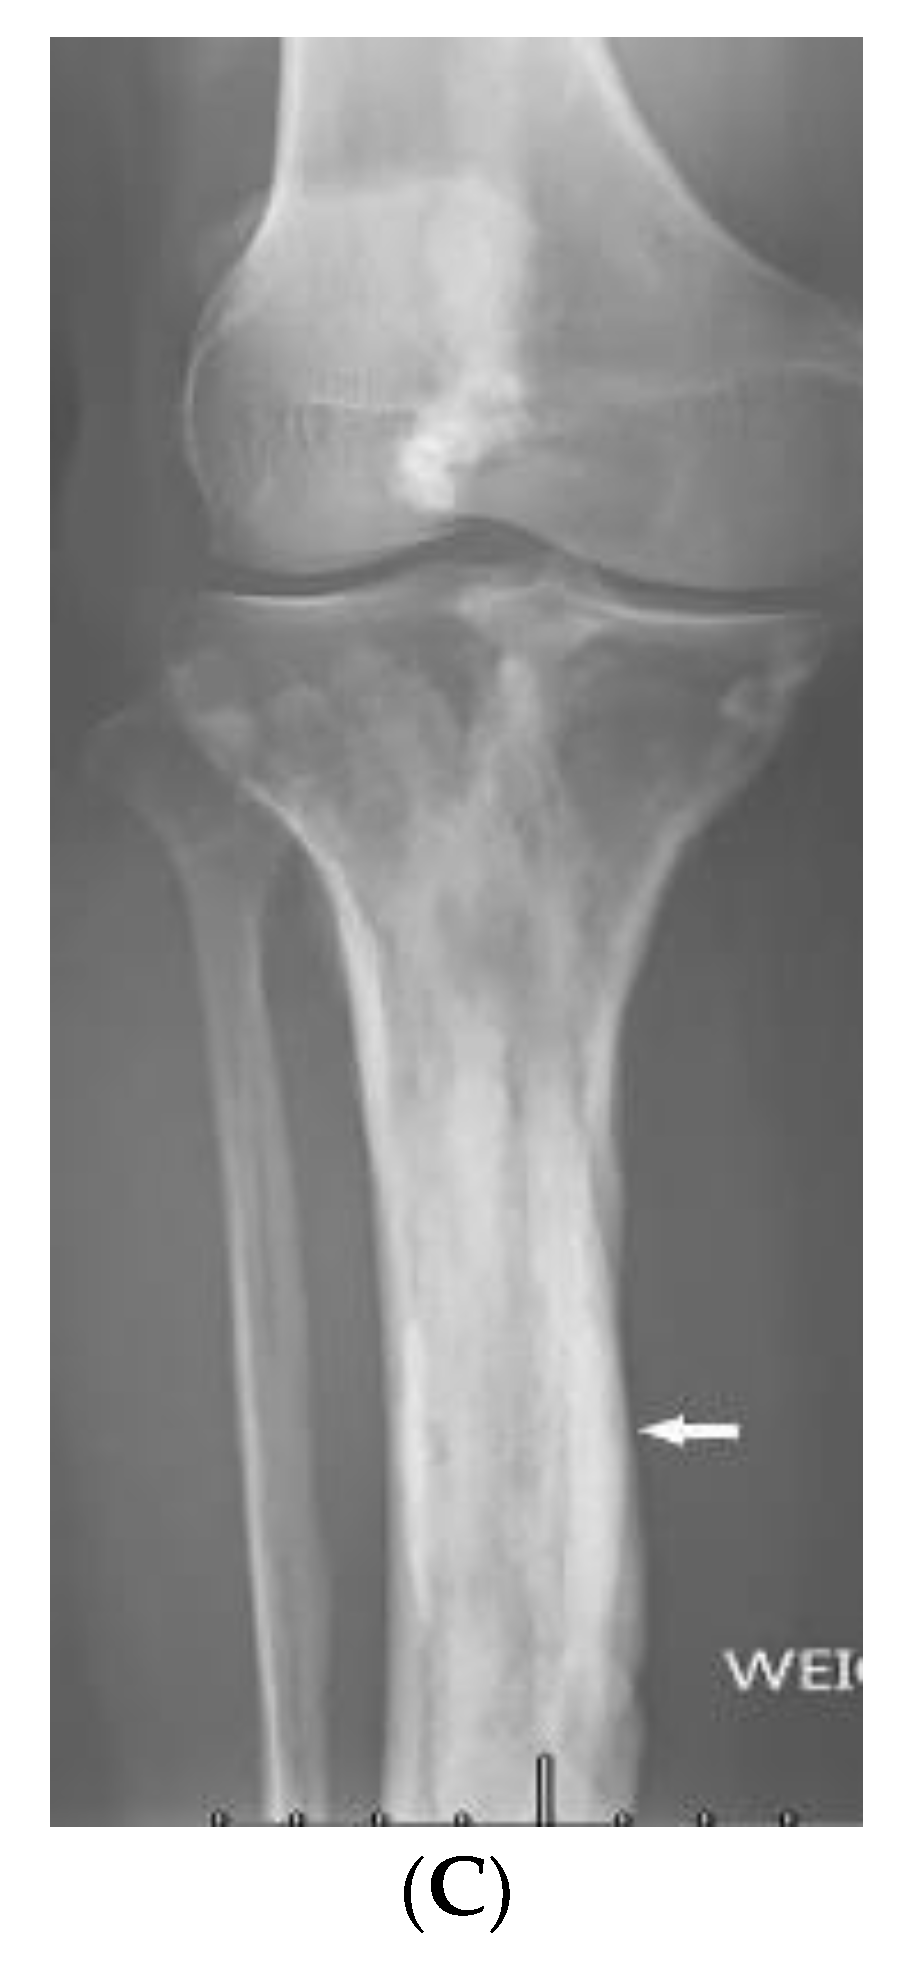

3.11. Buschke–Ollendorff Syndrome

| Buschke–Ollendorff syndrome | Dermatofibrosis lenticularis disseminata Osteopoikilosis Melorheostosis | Bony islands and multiple sclerotic lesions cause mottled appearance Cortical thickening with undulating bone |